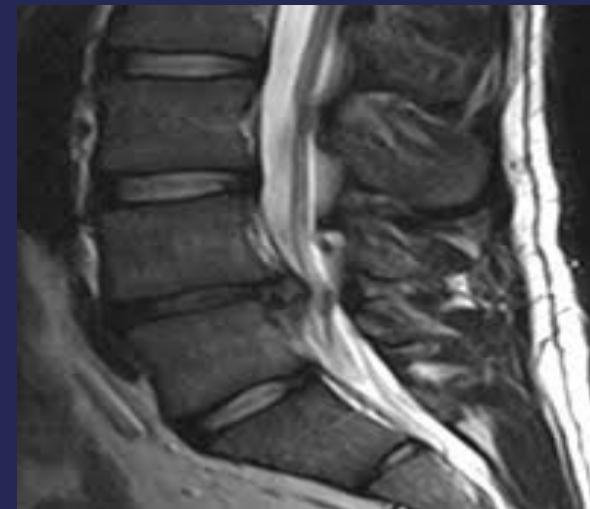

MRI:

- Gold standard for identifying disc pathology and localizing lesions

- Shows:

- Disc sequestration

- Disc bulge/protrusion

- MRI:

- Gold standard for disc identification and lesion localization